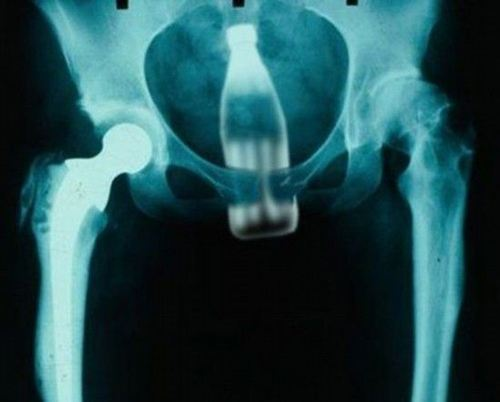

即使插入异物的患者被设置为避孕套中的外部物体,它们也总是使用“错误地滑动”作为翻译。

例如,说“efileta综合症”的患者:

人类的性是自由的,但略微满足一个特殊的瓶子。